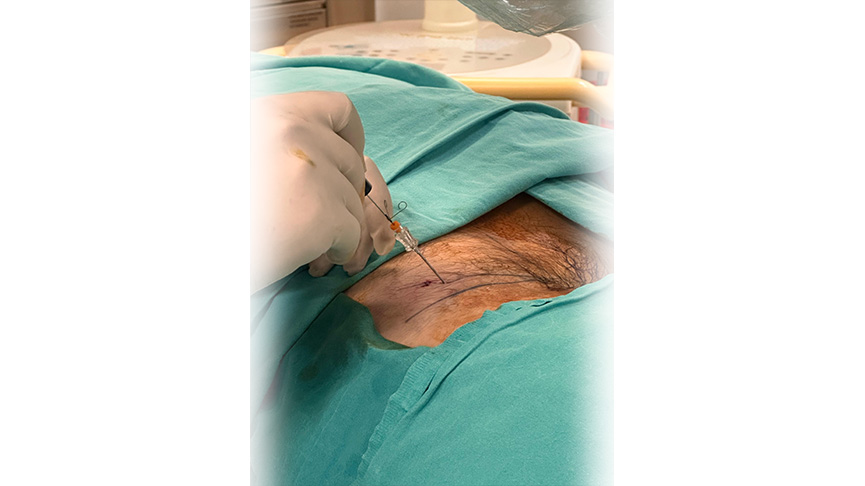

Yöntem: Uygulama lokal ve/veya sedayon anestezi altında yapılır. İşlem öncesinde skopi denilen anlık röntgen çekimi yapan cihaz ile doğru nokta belirlenir

İğne ve Ekipman: Daha sonrasında özel bir iğne veya kateter kullanılarak işlem yapılır. İğne, diskin iç kısmına yerleştirilir ve Plazma RF enerjisi ile işlem yapılır.